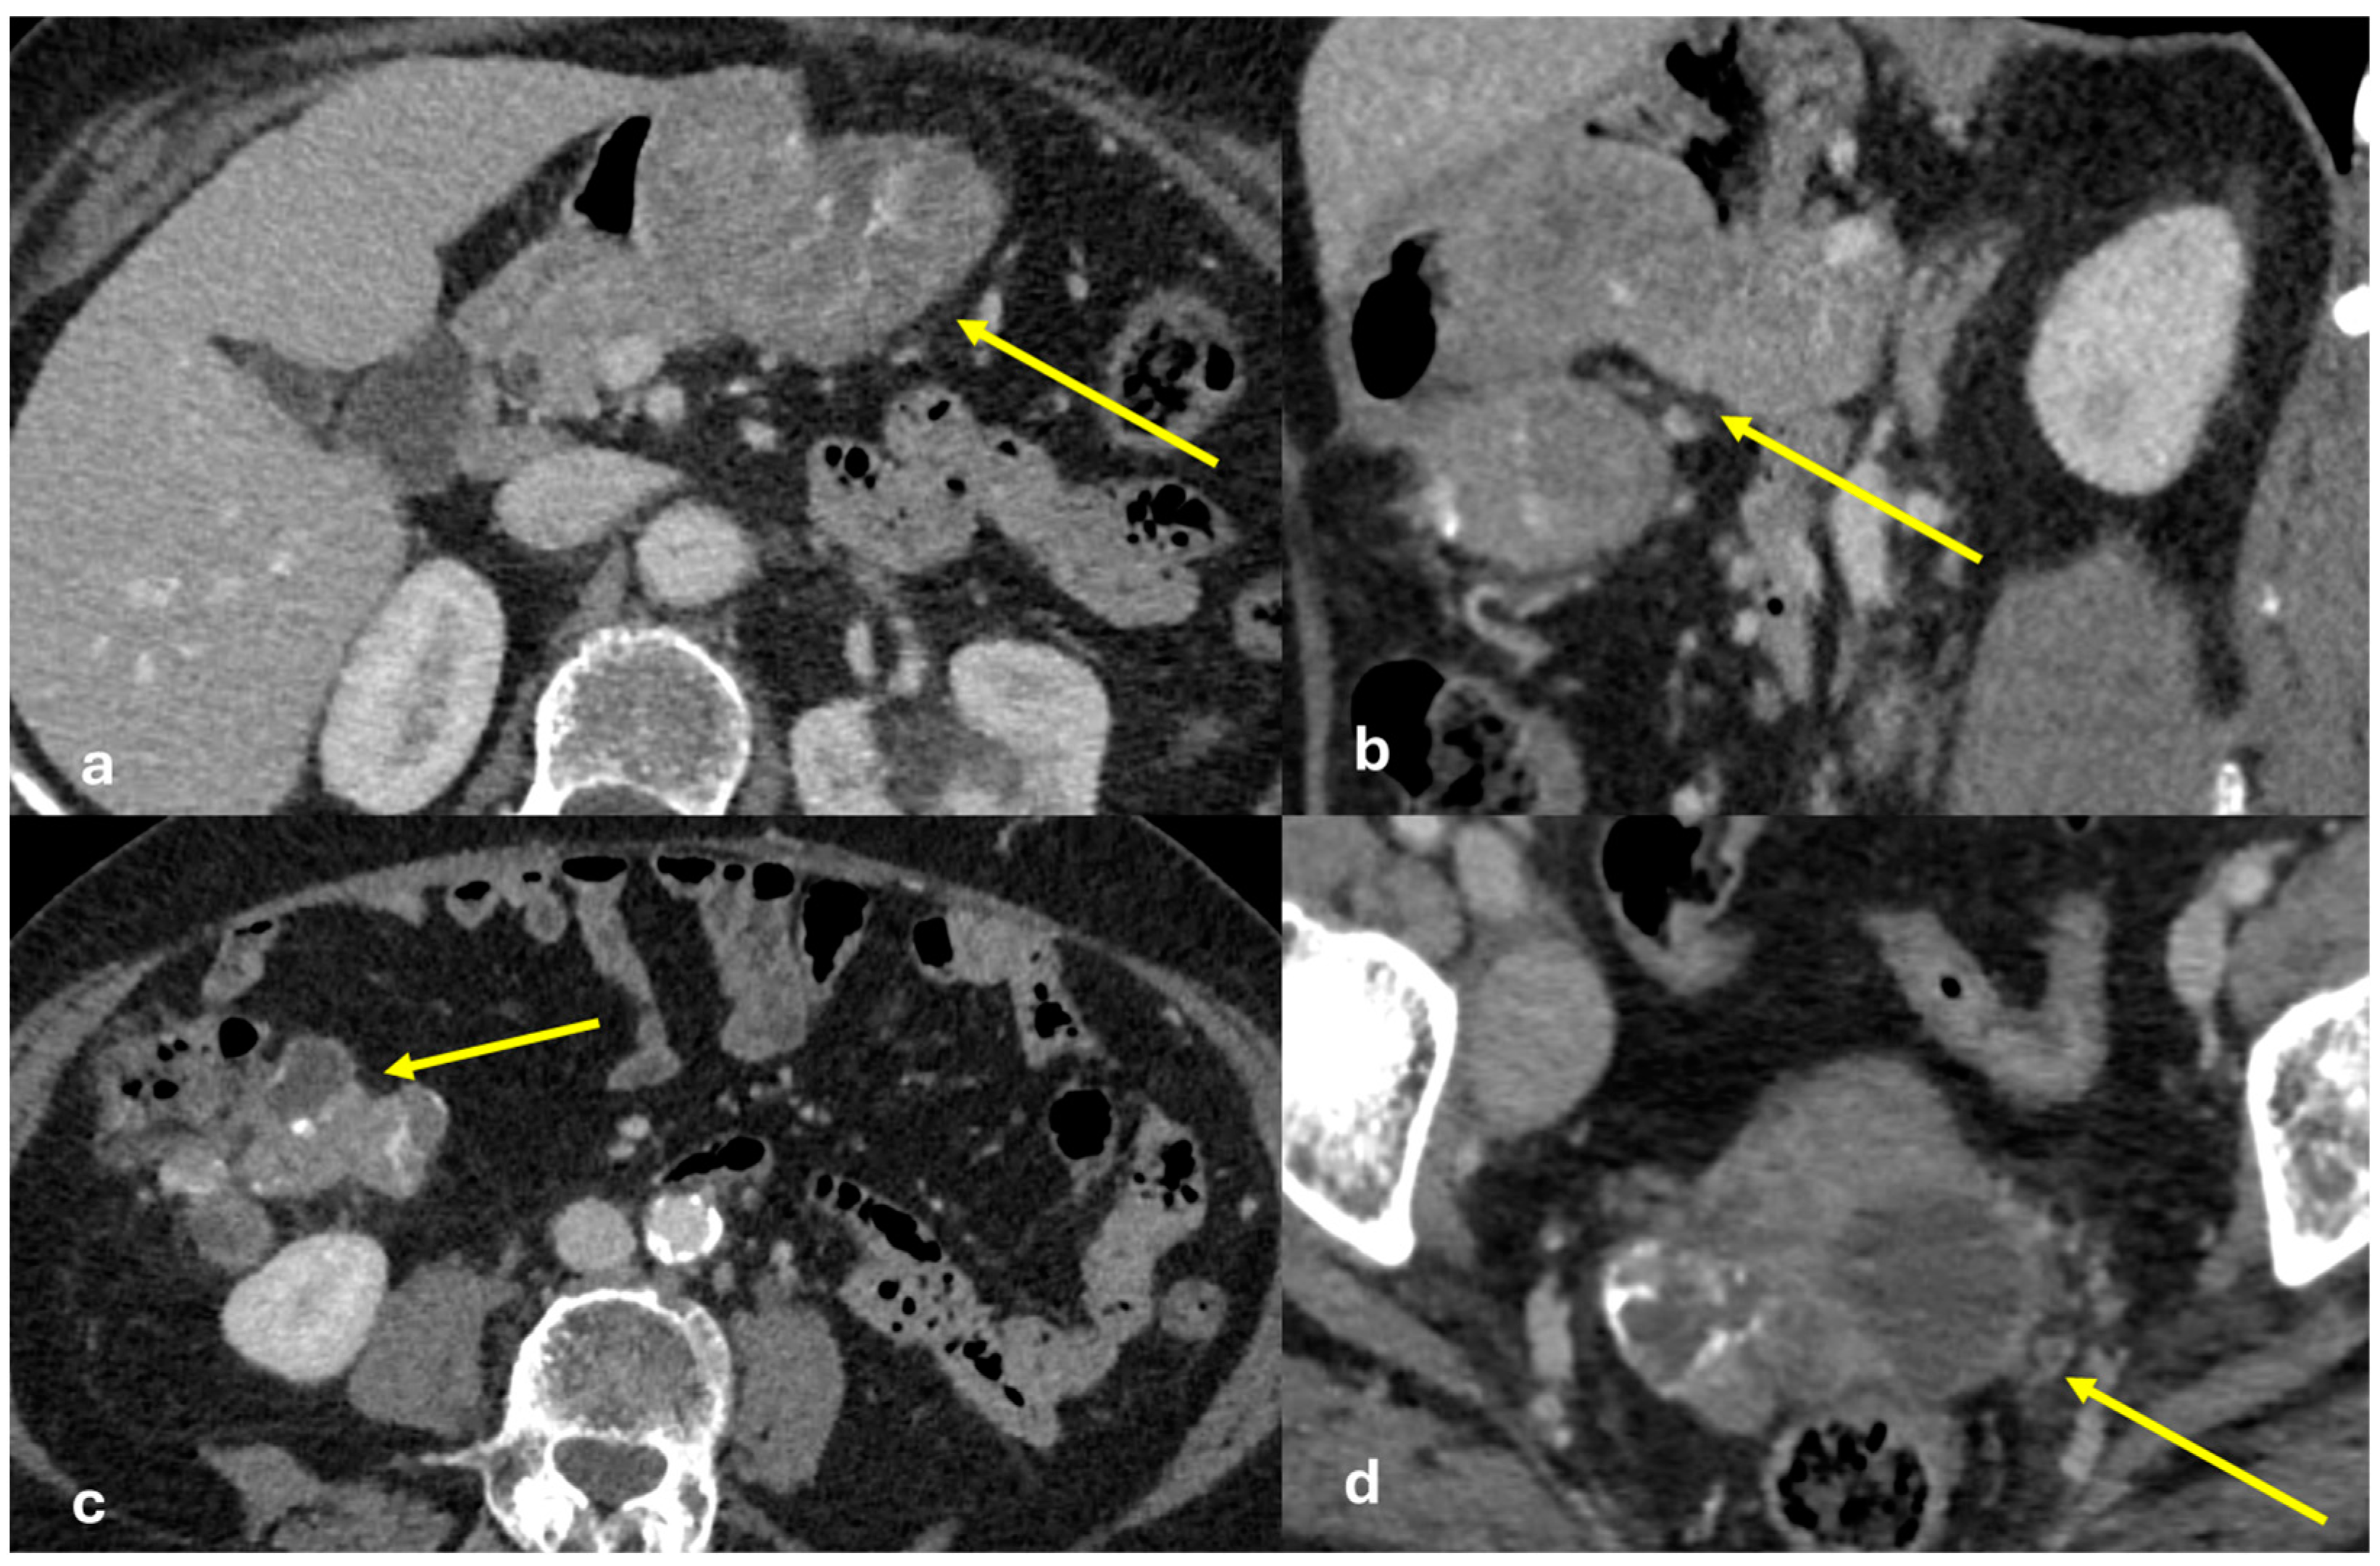

- Micro-nodular pattern: micro-nodules with a diameter ≤ 5 mm (Figure 1);

- Nodular pattern: nodules with a diameter > 5 mm (Figure 2a);

- “Omental cake”: nodular thickening of the omentum (Figure 2b);

- Plaque pattern: confluent nodular plaques, typically involving the lower surface of the right diaphragm (Figure 3);